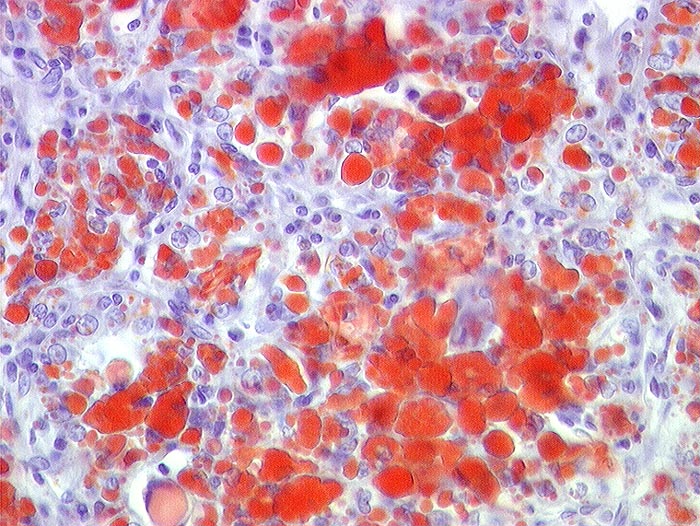

Nierenzellkarzinom: intrazellulärer Lipidnachweis

Mit Sudanrot angefärbte intrazelluläre Lipidtropfen in einem hellzelligen Nierenzellkarzinom

gelber Tumor (Lipid!) mit Einblutungen